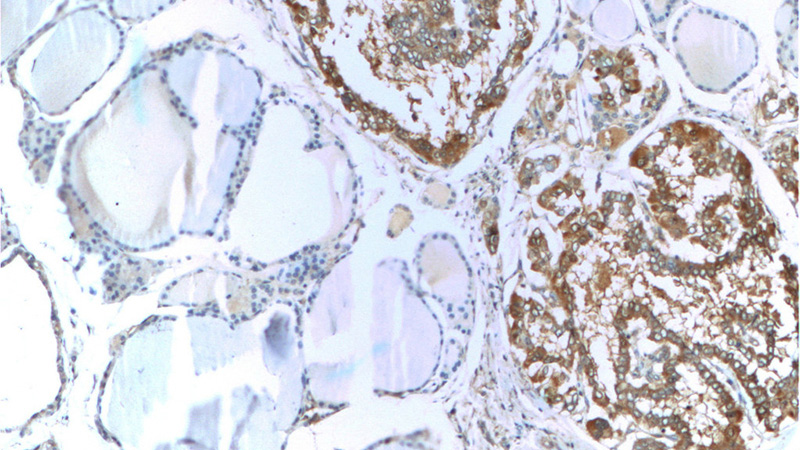

Galectin-3 Mouse Monoclonal antibody. Positive WB detected in Hela cells. Positive IHC detected in human thyroid cancer tissue, human colon tissue. Positive IF detected in MCF-7 cells. Observed molecular weight by Western-blot: 31 kDa

Immunohistochemistry of paraffin-embedded human thyroid cancer tissue slide using Catalog No:107286(Galectin 3 Antibody) at dilution of 1:100 (under 10x lens)